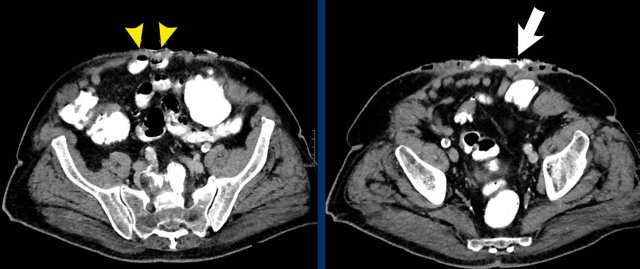

This patient has two hernias.

There is a midline hernia (yellow arrowheads) and a lateral hernia (white arrowheads).

in this case the total combined length and total width are measured.